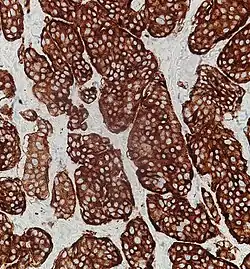

Neuroendocrine tumors, despite differing embryological origin, have common phenotypic characteristics. NETs show tissue immunoreactivity for markers of neuroendocrine differentiation (pan-neuroendocrine tissue markers) and may secrete various peptides and hormones. There is a lengthy list of potential markers in neuroendocrine tumors; several reviews provide assistance in understanding these markers.[70][60] Widely used neuroendocrine tissue markers are various chromogranins, synaptophysin and PGP9.5. Neuron-specific enolase (NSE) is less specific.[1][8] The nuclear neuroendocrine marker insulinoma-associated protein-1 (INSM1) has proven to be sensitive as well as highly specific for neuroendocrine differentiation.[71]